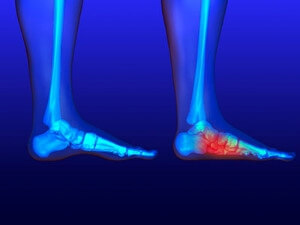

Gout, typically found in diabetic patients, is an unusually painful form of arthritis caused by elevated levels of uric acid in the bloodstream. The condition typically strikes the big joint on the big toe. It has also been known to strike the knees, elbows, fingers, ankles and wrists—generally anywhere that has a functioning, moving joint.

The high level of uric acid in a person’s bloodstream creates the condition known as hyperuricema—the main cause of gout. Genetic predisposition occurs in nine out of ten sufferers. The children of parents who suffer gout will have a two in ten chance of developing the condition as well.

This form of arthritis, being particularly painful, is the leftover uric acid crystallizing in the blood stream. The crystallized uric acid then travels to the space between joints where they rub, causing friction when the patient moves. Symptoms include: pain, redness, swelling, and inflammation. Additional side effects may include fatigue and fever, although reports of these effects are very rare. Some patients have reported that pain may intensify when the temperature drops, such as when you sleep.

Most cases of gout are easily diagnosed by a podiatrist’s assessment of the various symptoms. Defined tests can also be performed. A blood test to detect elevated levels of uric acid is often used as well as an x-ray to diagnose visible and chronic gout.